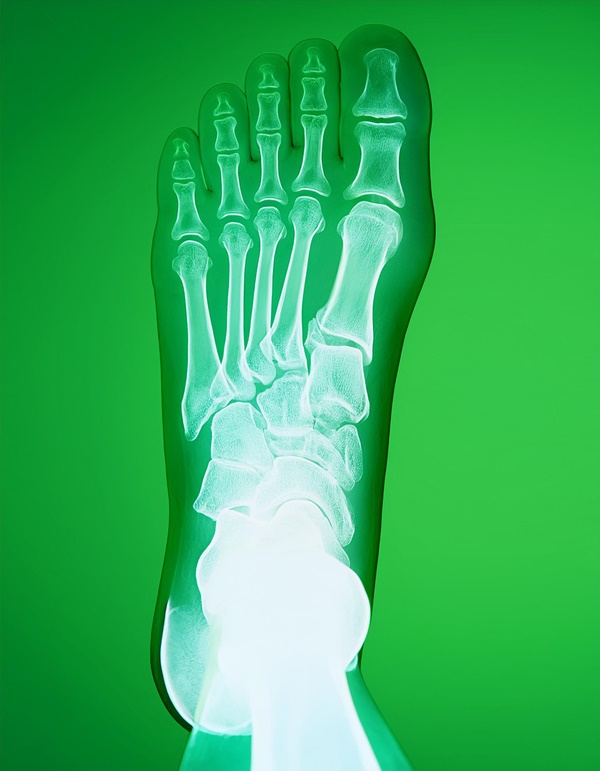

"나 요즘 눈뜨고 일어나서 첫발을 딛는 순간 너무 아파. 마치 바늘로 발바닥을 콕콕 찌르는 느낌이야." 처음엔 대수롭지 않게 넘겼는데, 그 말이 자꾸 마음에 걸렸어요. 알고 보니 족막염 증상이더라고요. 족막염은 발뒤꿈치에서 발가락까지 연결된 '족저근막'이라는 조직에 염증이 생긴 걸 말하는데요. 아침이나 오래 앉아 있다가 일어날 때, 처음 걸음마처럼 발을 내디딜 때 심한 통증이 나타나죠.